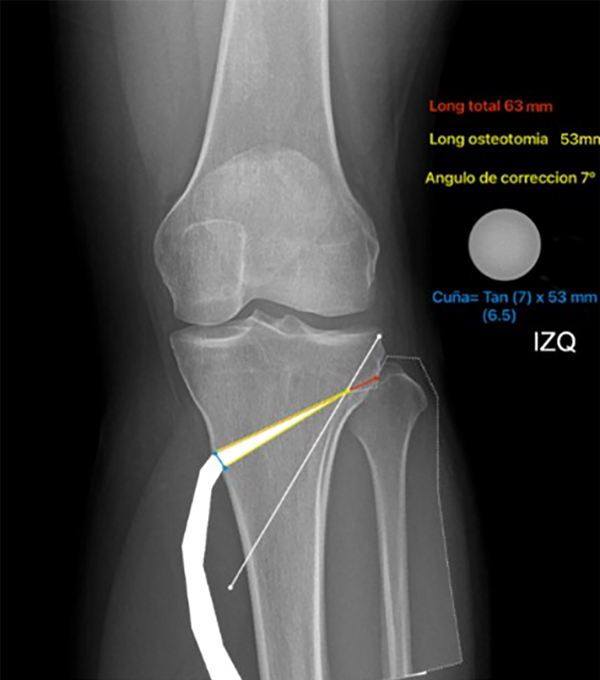

Si bien múltiples autores han descripto métodos y realizado tablas para saber los milímetros de apertura de la osteotomía,31 actualmente se utiliza un método trigonométrico para determinar la altura de la cuña usando la siguiente ecuación: y = x tan(θ), donde “y” es la altura de la cuña, “x” es el ancho real de la tibia al nivel de la osteotomía planificada, línea dirigida a la articulación tibioperonea, y “θ” es el ángulo de corrección deseado32 (figs. 11 y 12).

Figura 11: Cálculo de apertura de la osteotomía: la cuña = tangente (7° corrección), x longitud de osteotomía (53 mm), el resultado es el otro lado del triángulo (los mm de apertura de la osteotomía), en este caso es 6.5 mm.

Figura 12: Cálculo de apertura de la osteotomía: la línea roja más la amarilla es la distancia completa (63 mm) en el nivel de la osteotomía desde la cortical medial hasta la lateral, la línea amarilla (53 mm) corresponde a la longitud exacta de la osteotomía restando 10 mm a la línea roja (distancia para la bisagra lateral), la línea blanca corresponde al pin de protección de la bisagra (dirigido al área subcondral platillo lateral y a 10 mm de la cortical lateral).